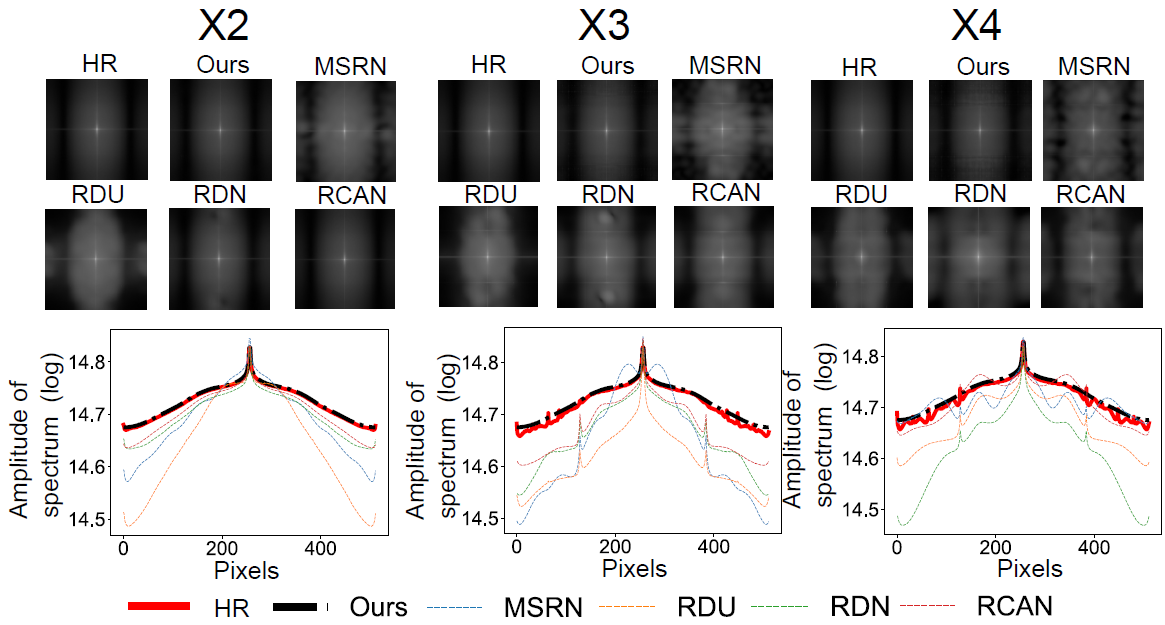

3.6 Analysis on spectral bias

We perform frequency analysis to evaluate the spectral bias of our frequency-aware model and other DL algorithms. We apply 2D DFT to the HR and SR OCT images, after which we average the logarithm of the intensities for each A-line and plot the intensity values over the pixels. The frequency analysis is carried out by averaging the spectrum of the SR OCT images. The results are reported in Fig 3. As shown in Fig 3 (a), our frequency-aware model generates SR images with averaged spectrums that are similar to the HR images. The summed intensities for pixels, as shown in Fig 3 (b), confirm our frequency-aware model are less biased in spectrum distribution compared with other DL algorithms. On the other hand, existing DL algorithms generate SR OCT images with spectral bias in an unstable manner, as confirmed by Fig 3.

3.7 Quantitative analysis on super-resolution performance

We compare the quantitative performance of our frequency-aware model to other DL algorithms. As shown in Table 1, our frequency-aware model generates SR OCT images with better PSNR, SSIM, and SFD scores compared to other deep learning algorithms. Together with Fig 3, we confirm our frequency-aware model generates SR OCT images with better spatial and frequency properties compared to other DL algorithms.